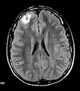

Tuberous sclerosis

Tuberous sclerosis complex (TSC) is a rare multisystem autosomal dominant genetic disease that causes non-cancerous tumours to grow in the brain and on other vital organs such as the kidneys, heart, liver, eyes, lungs and skin. A combination of symptoms may include seizures, intellectual disability, developmental delay, behavioral problems, skin abnormalities, lung disease, and kidney disease. [Source: Wikipedia ]